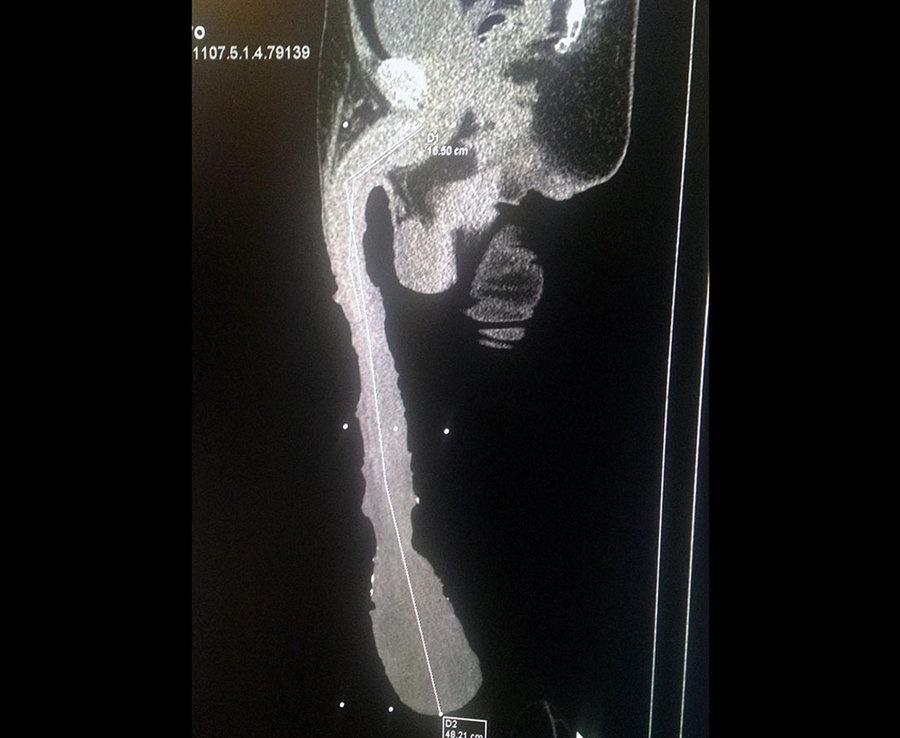

«Διαπιστώσαμε ότι το δέρμα στο πέος του είναι ασυνήθιστα τραβηγμένο και φθάνει μέχρι το γόνατό του», ανέφερε από την πλευρά του ο ακτινολόγος Jesus Pablo Gil Muro, αποκαλύπτοντας: «Οι αδένες όμως δεν φθάνουν μέχρι κάτω, αλλά είναι μήκους περίπου 15 εκατοστών».

Ανταμοιβή του ήταν η δημοσιότητα που έλαβε το 2015, όταν ένα βίντεό του έγινε viral και αυτός επίσημα ο άνδρας με το μεγαλύτερο πέος στην κόσμο, ξεπερνώντας με τα 48 εκατοστά του τα μόλις… 34 του Αμερικανού ηθοποιού Jonah Falcon.